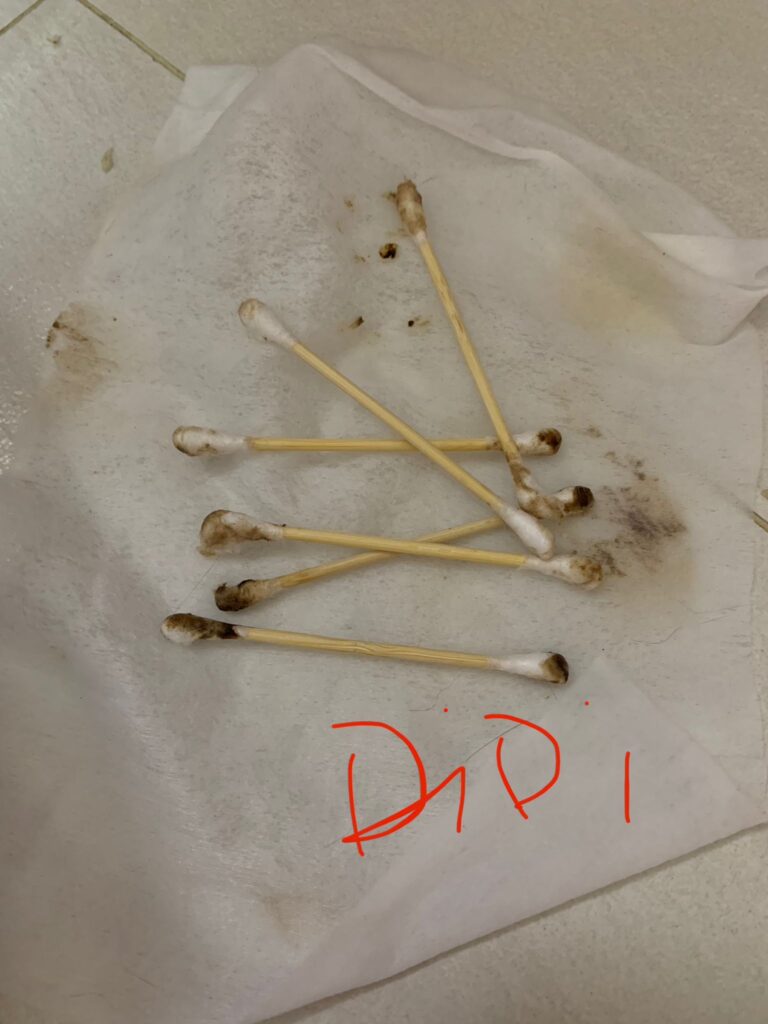

Morning: cut nails and clean ears

11am+: Cut nails, clean ears.

Noon: cut nails and clear ears – nails long and ears dirty. he is the first to q up.